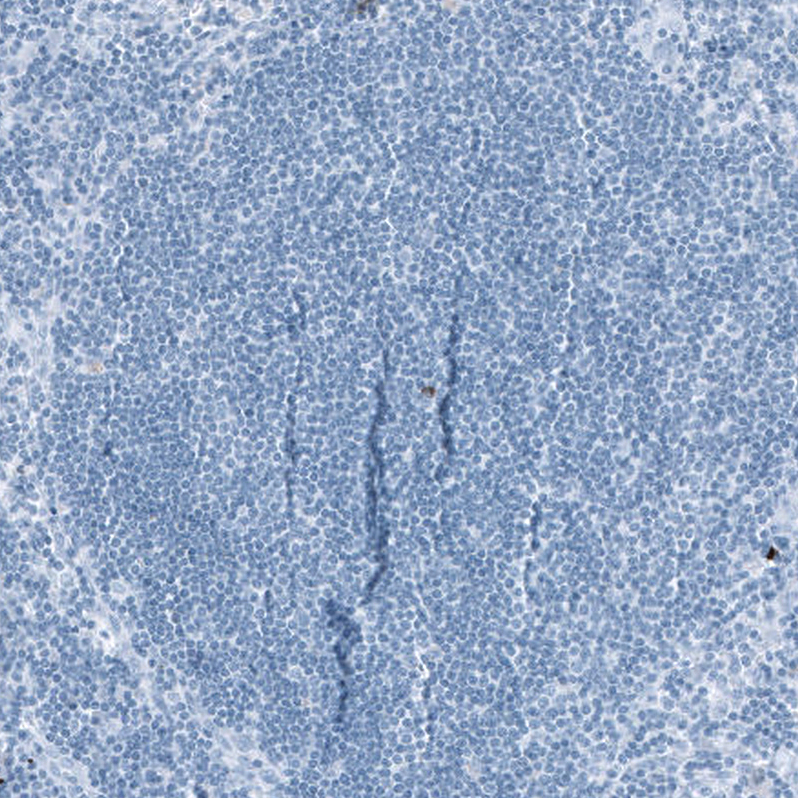

Immunohistochemical staining of human cerebellum shows moderate positivity in neuropil.